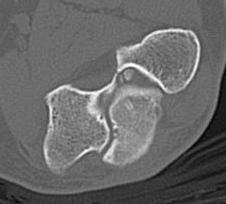

CT

Define olecranon and coranoid process osteophytes

Identification loose bodies

Osteophyte of the olecranon likely impinging in extension

CT demonstrating loose bodies in the ulnohumeral joint

Multiple loose bodies in anterior and posterior elbow joint